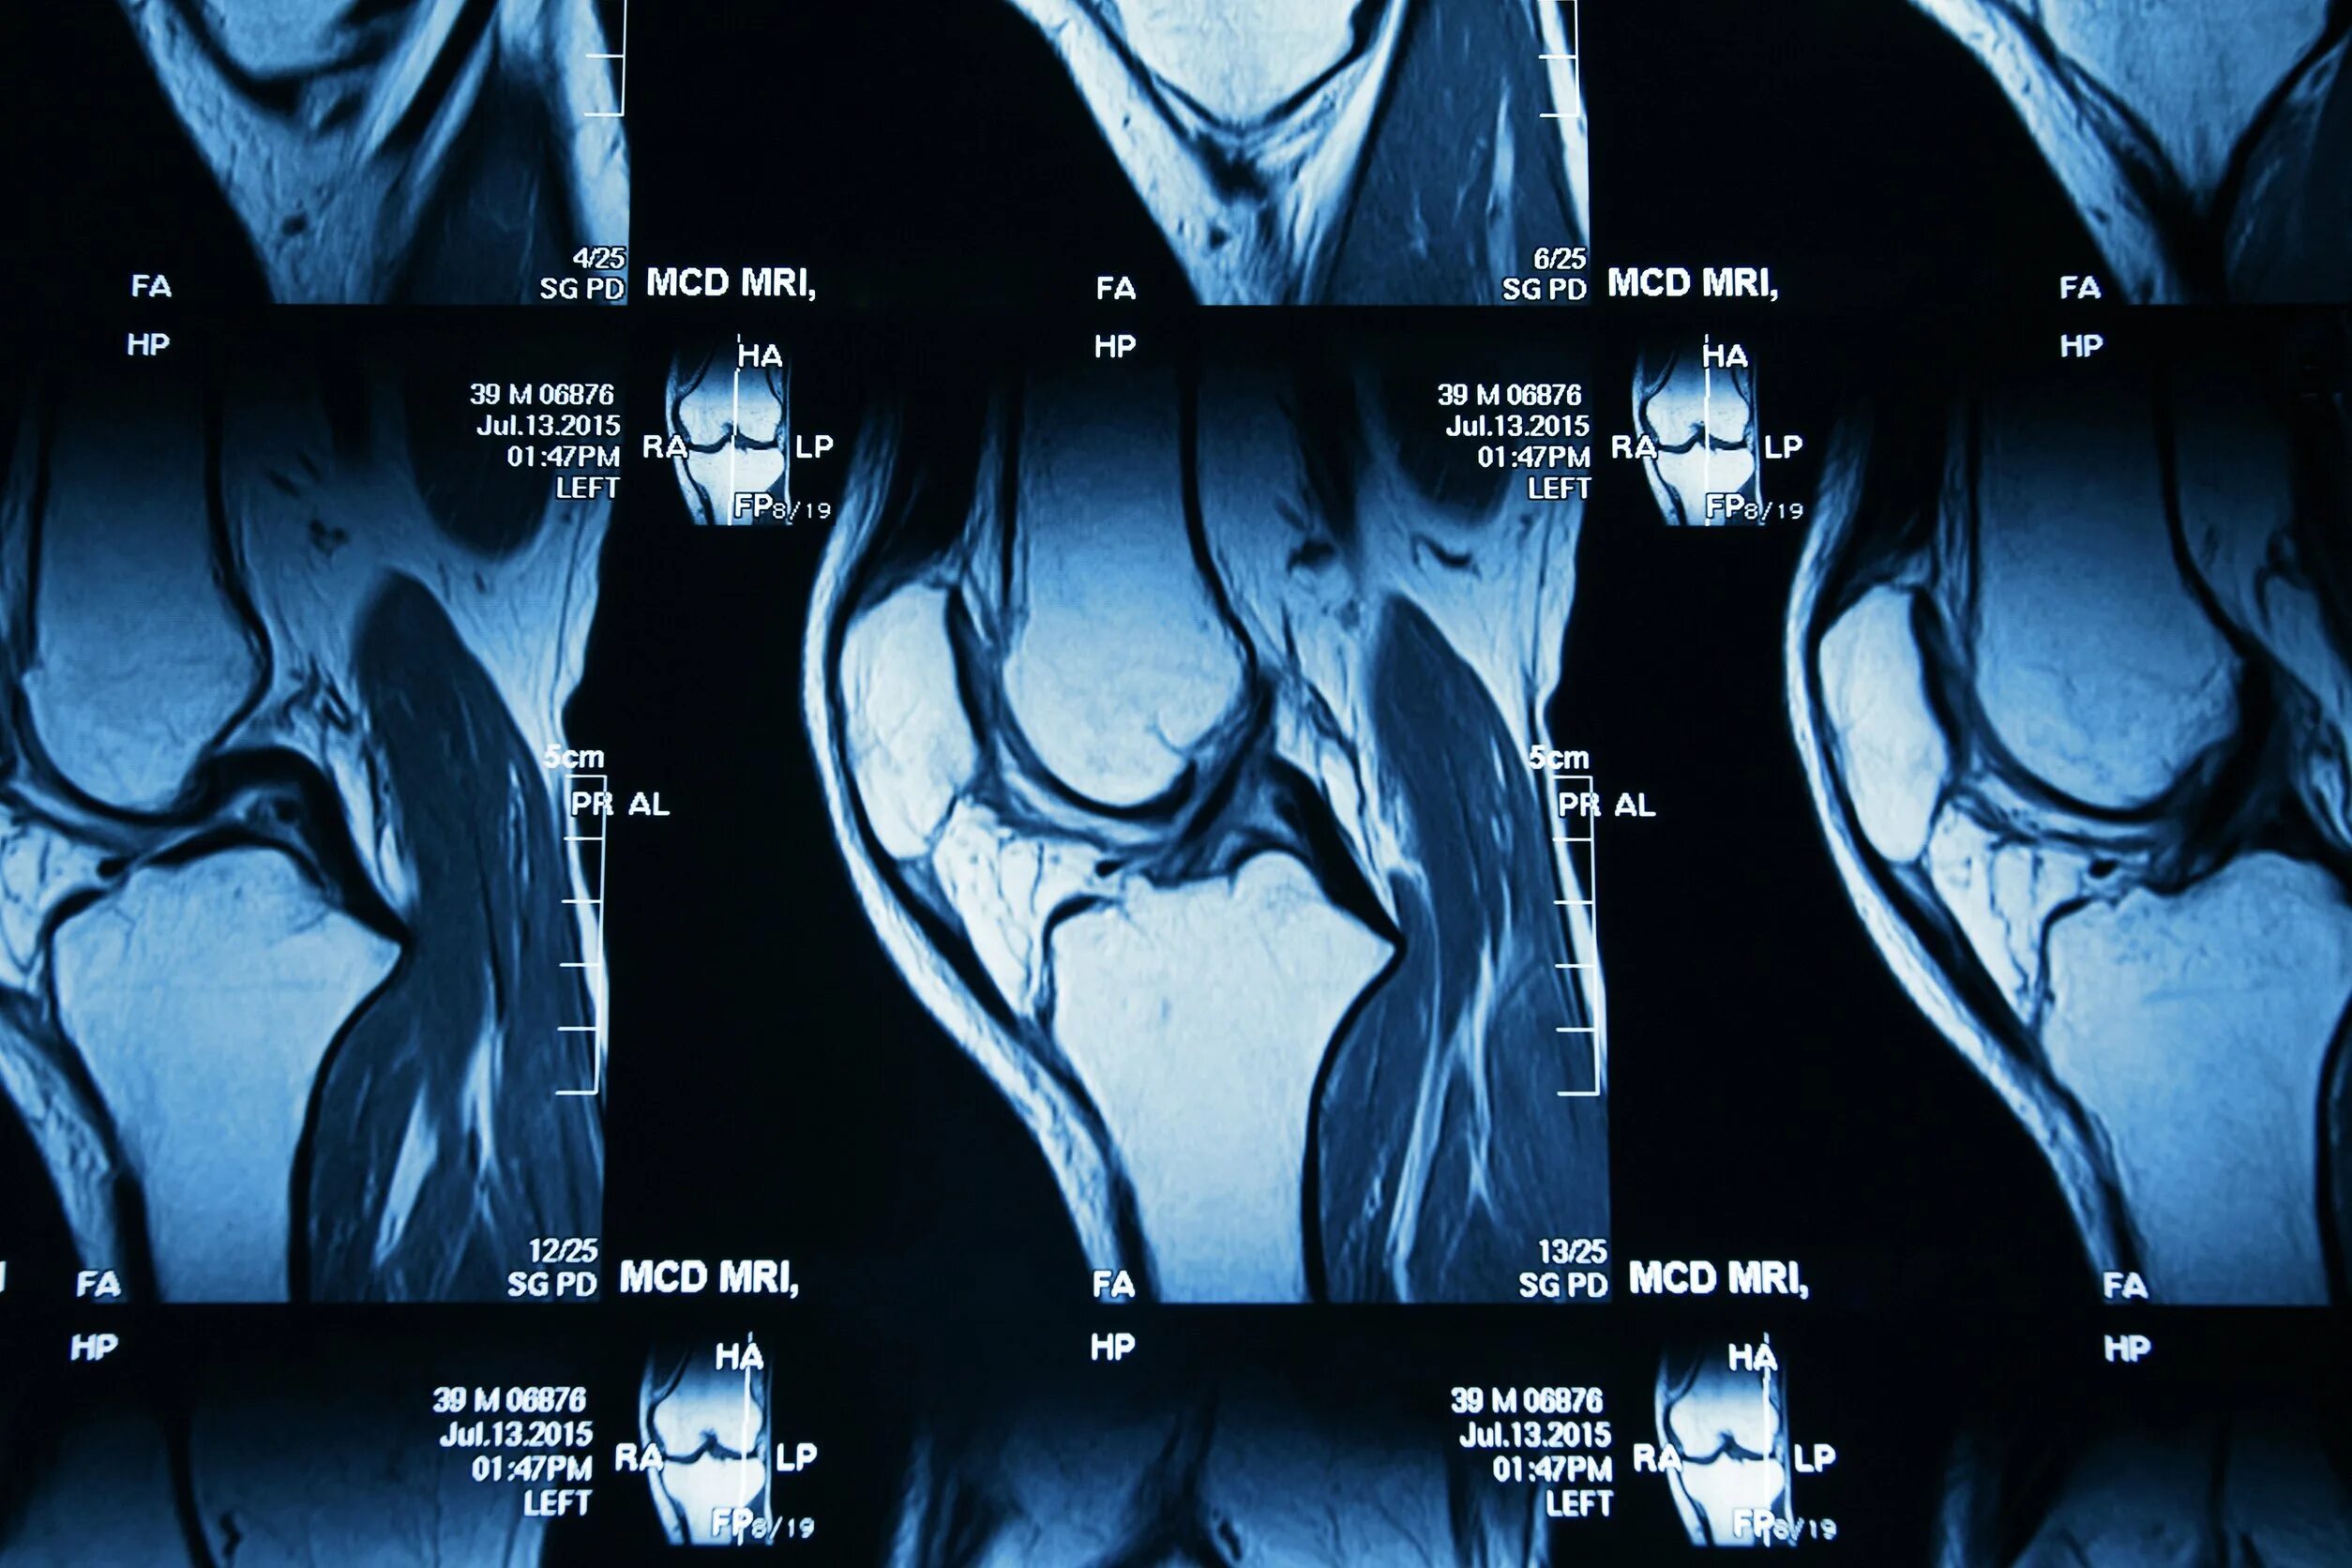

Мрт коленного сустава набережные